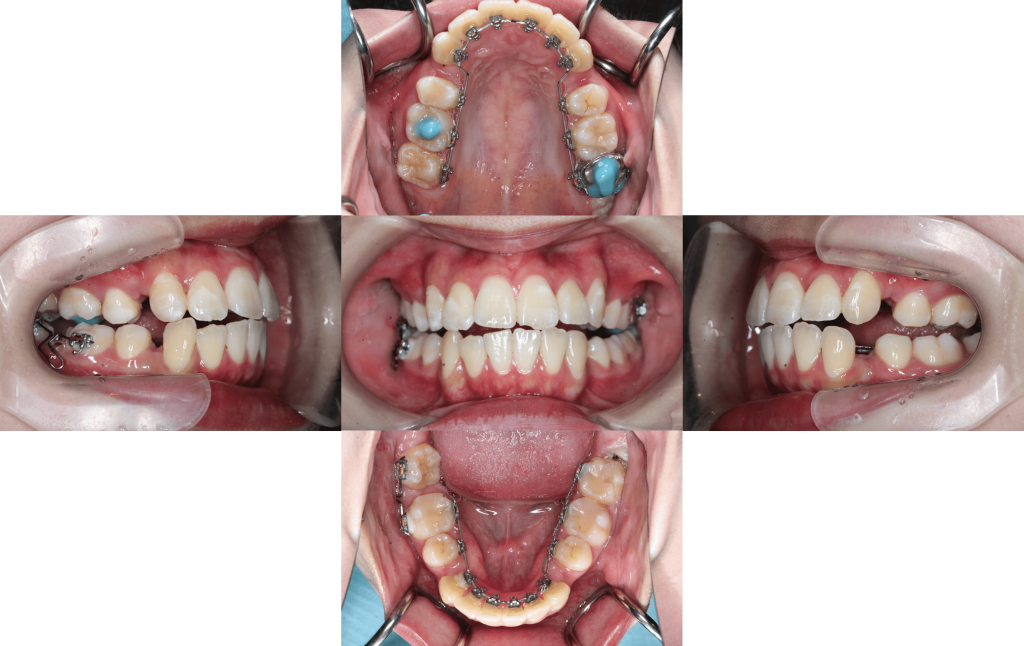

装置装着

約6か月後